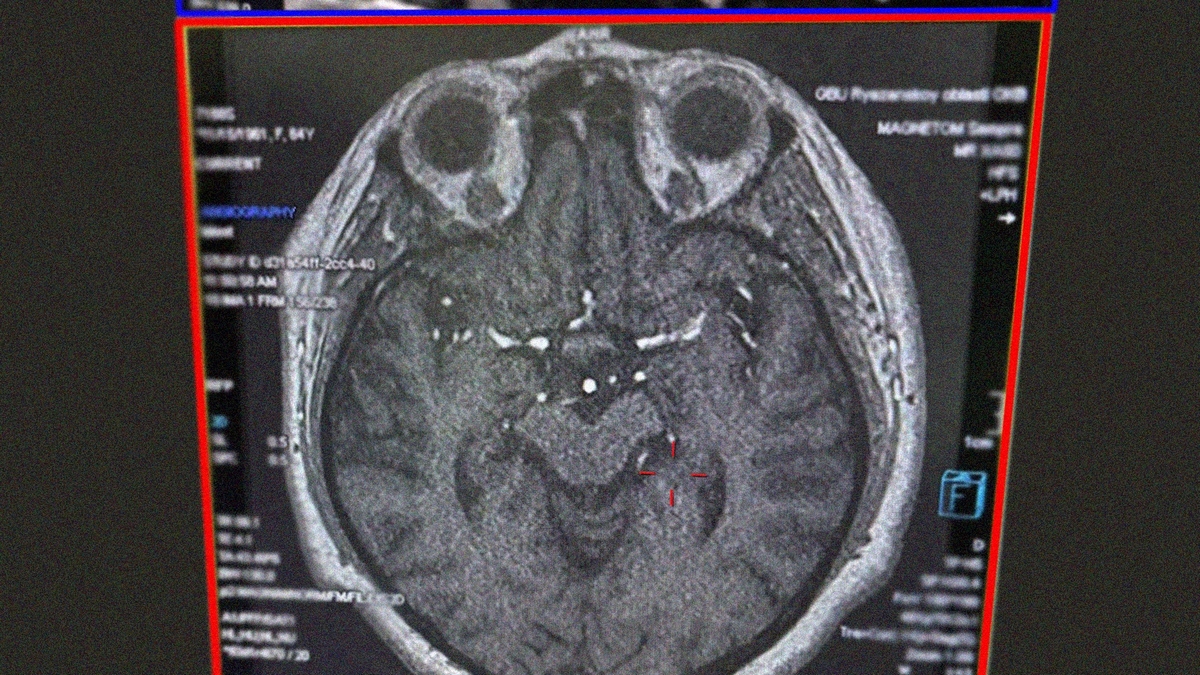

Врачи Рязанской ОКБ помогли 80-летней пенсионерке восстановиться после инсульта

Врачи Рязанской областной клинической больницы помогли 80-летней пенсионерке восстановиться после инсульта. Об этом сообщила пресс-служба министерства здравоохранения.

Женщину без сознания обнаружила соседка, она же вызвала скорую. Женщине провели тромболизис. Спустя девять дней пациентка начала чувствовать себя удовлетворительно – она могла самостоятельно передвигаться, восстанавливалась речь. К инсульту, как выяснилось, привело то, что пенсионерка много лет курила, ела жирную, жареную и пересоленную пищу.

Фото: министерство здравоохранения Рязанской области